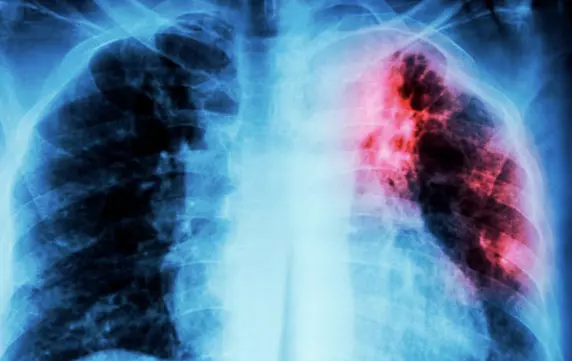

Saltillo, Coah.- Durante la temporada invernal, la tuberculosis es una de las enfermedades que se mantiene bajo vigilancia epidemiológica en Coahuila, ya que en promedio se llegan a detectar hasta 700 casos por año.

Explicó que la presencia de una tos persistente que se extiende por más de 15 días, es la principal señal de alerta y en la que se determina que los pacientes se realicen una prueba de detección.